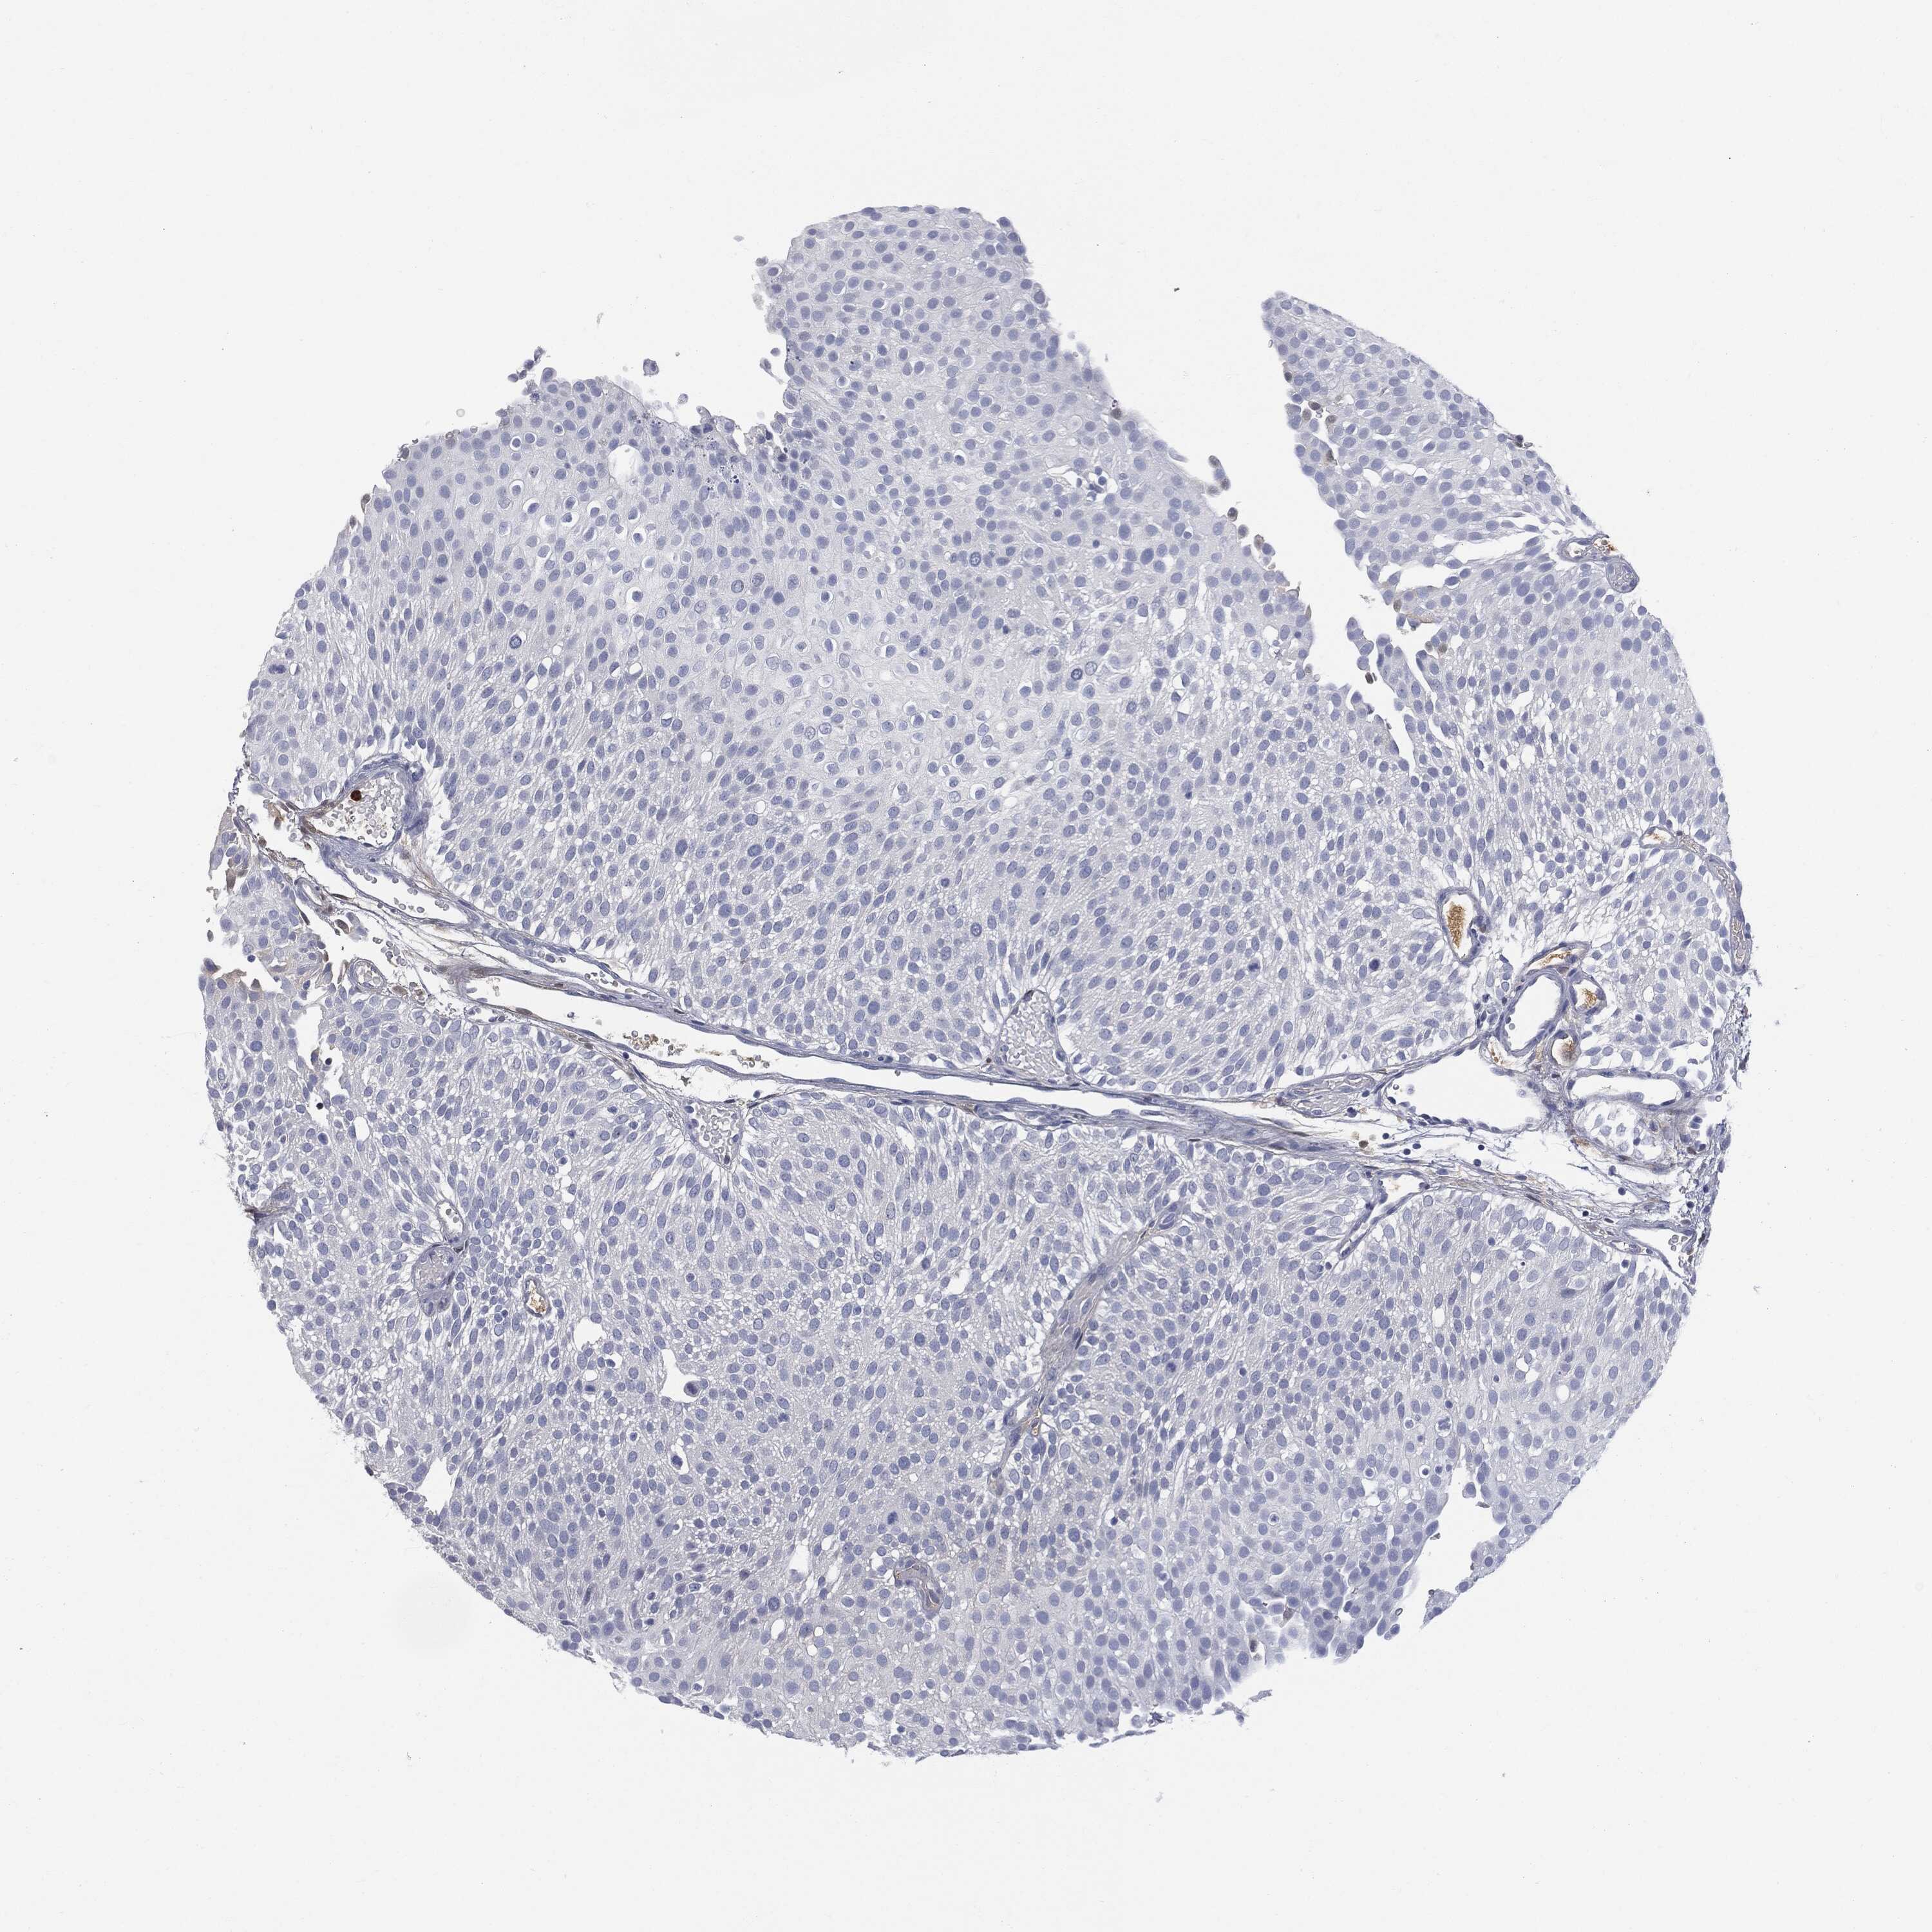

UROTHELIAL CANCER - Protein expressioni

A mouse-over function shows sample information and annotation data. Click on an image to view it in a full screen mode. Samples can be filtered based on level of antibody staining by selecting one or several of the following categories: high, medium, low and not detected. The assay and annotation is described here.

Note that samples used for immunohistochemistry by the Human Protein Atlas do not correspond to samples in the TCGA dataset.

Antibody stainingi

Antibody staining in the annotated cell types in the current human tissue is reported as not detected, low, medium, or high, based on conventional immunohistochemistry profiling in selected tissues. This score is based on the combination of the staining intensity and fraction of stained cells.

Each image is clickable and will lead to virtual microscopy that enables deeper exploration of all samples and also displays staining intensity scores, fraction scores and subcellular localization as well as patient and tissue information for each sample.

Antibody HPA001198

Antibody HPA002028

Antibody CAB016689

Antibody CAB080300

Staining

High

Medium

Low

Not detected

Intensity

Strong

Moderate

Weak

Negative

Quantity

>75%

75%-25%

<25%

None

Location

Nuclear

Cytoplasmic/membranous

Cytoplasmic/membranous,nuclear

Urothelial carcinoma, High grade

Urothelial carcinoma, Low grade

Adenocarcinoma, NOS